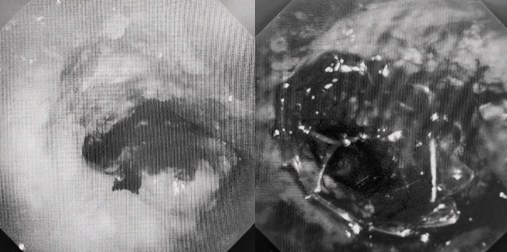

時(shí)間就是生命!了解患者病情后,歐陽海峰立刻啟動氣道梗阻緊急救治通道,協(xié)調(diào)院前轉(zhuǎn)運(yùn),急診快速入院流程。凌晨患者入院胸部CT顯示,現(xiàn)存唯一的呼吸通道在右主支氣管處,狹窄處僅約3毫米,患者命懸一線!

患者入院第二天,在麻醉手術(shù)中心全力配合下,歐陽海峰帶領(lǐng)呼吸介入團(tuán)隊(duì),歷時(shí)40分鐘快速置入硬質(zhì)支氣管鏡、鏟切腫瘤,并順利植入全覆膜TTS支氣管金屬支架?;颊邭舛贪Y狀即刻緩解,為患者贏得了寶貴的后續(xù)治療機(jī)會。